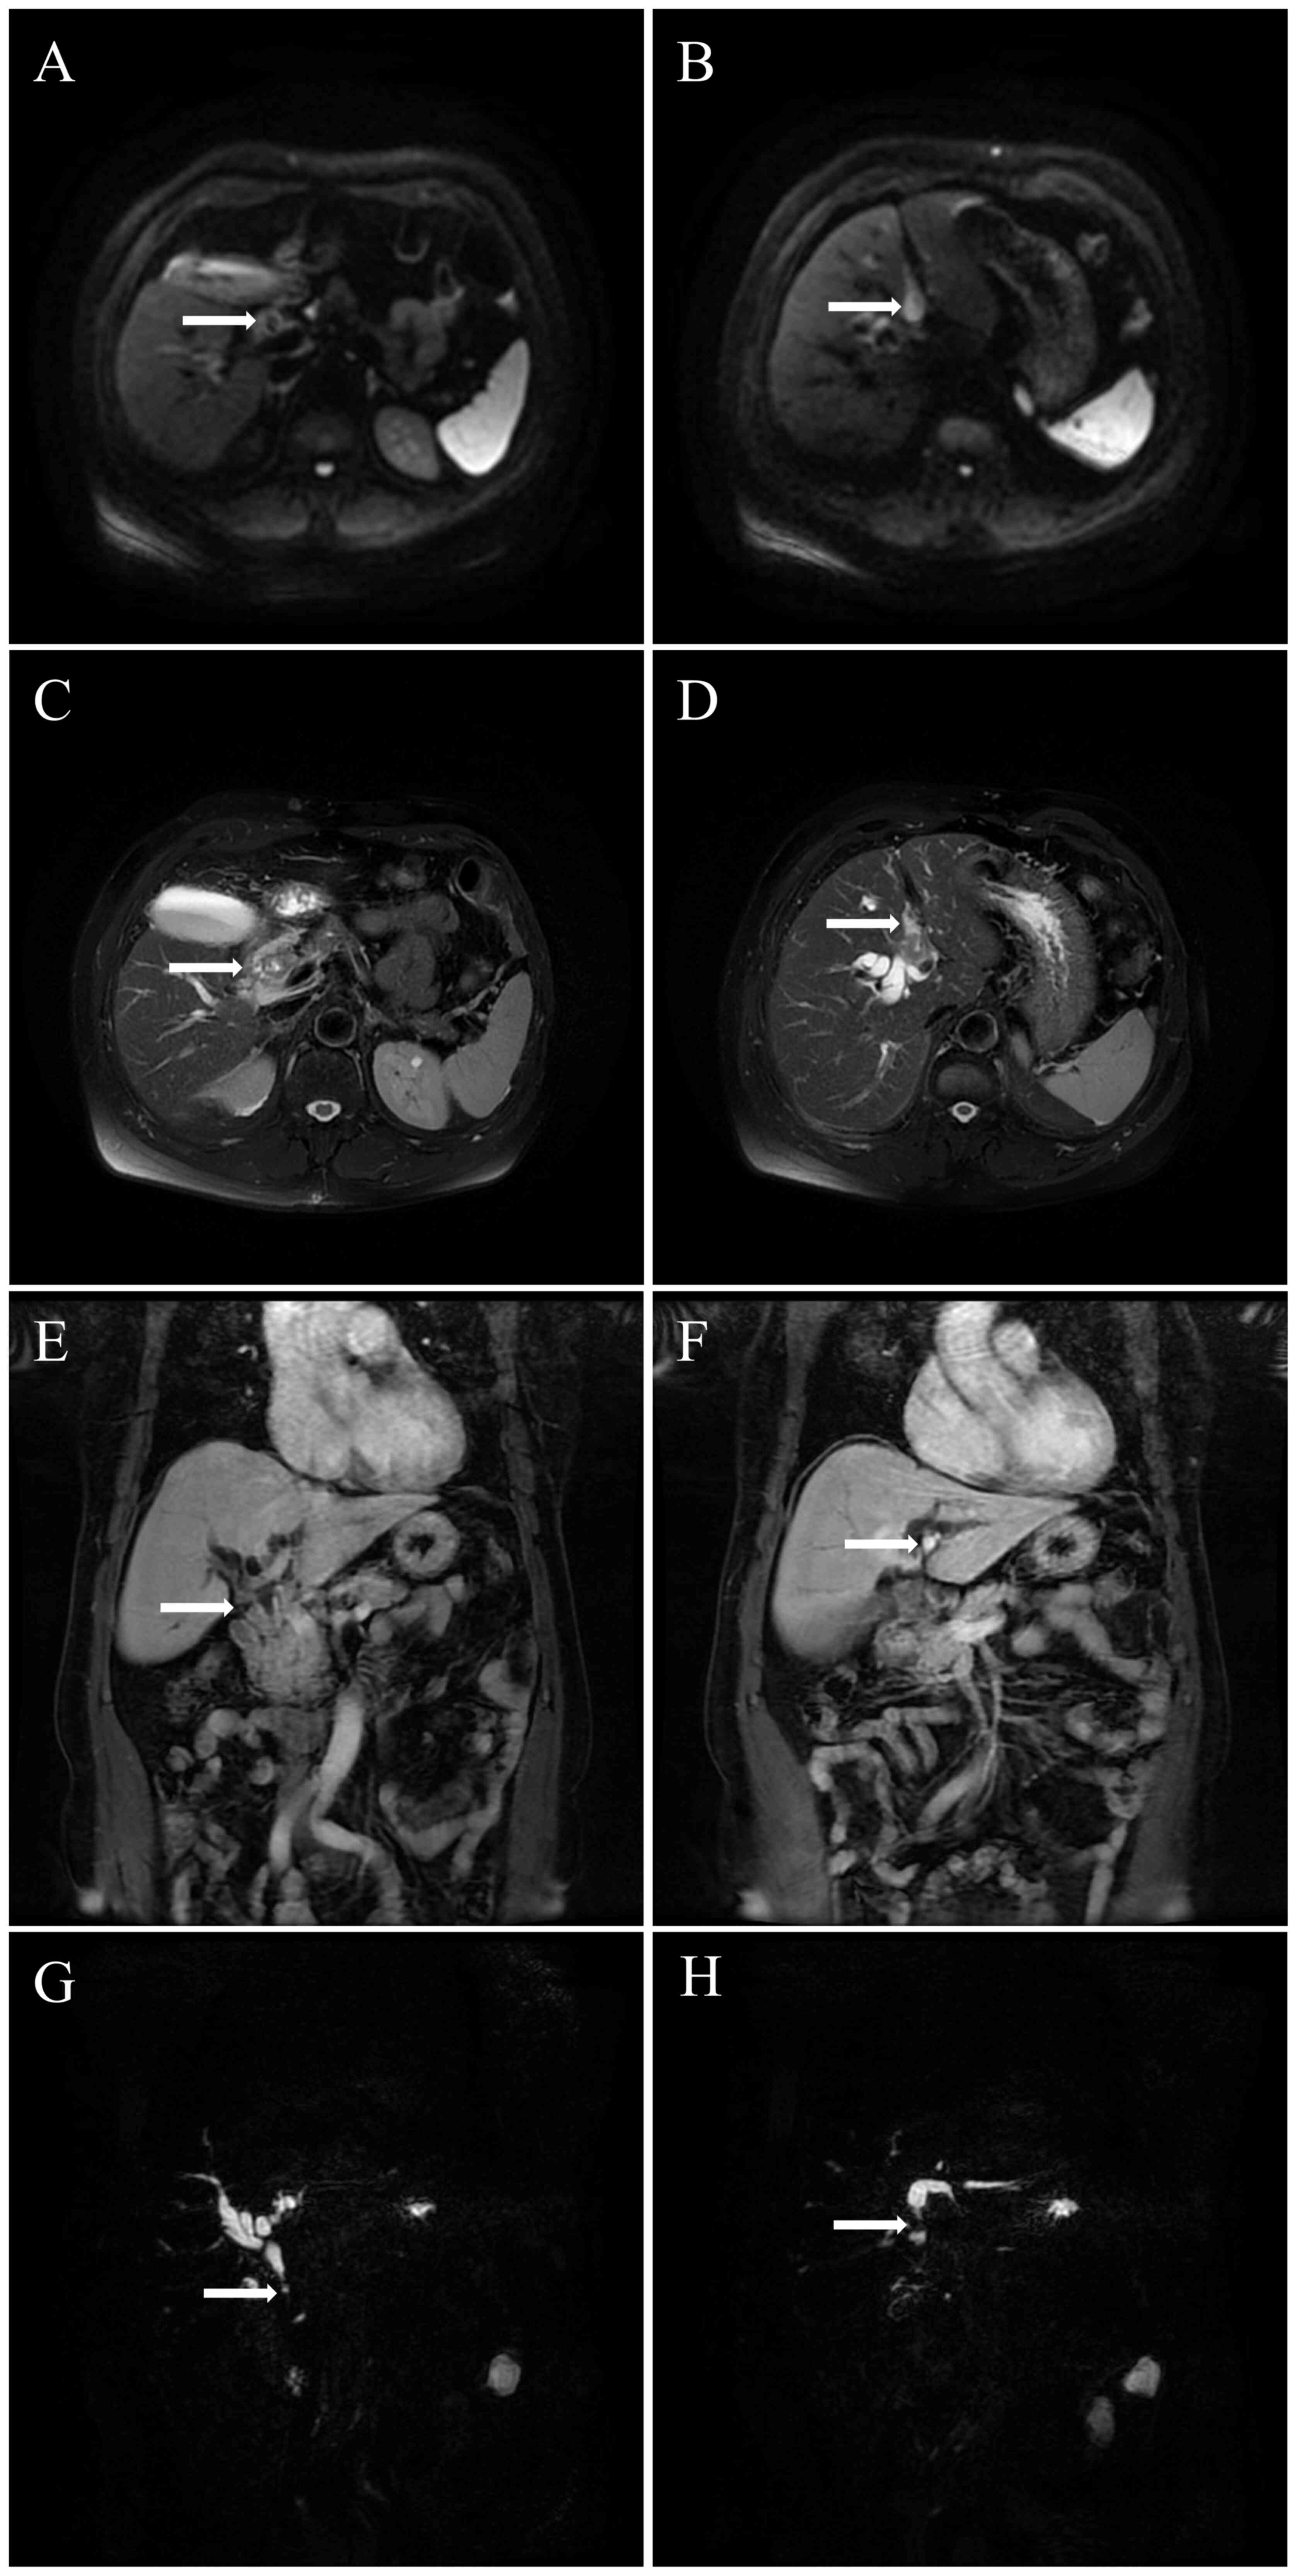

A 63-year-old male was admitted to Affiliated Jinhua Hospital, Zhejiang University School of Medicine (Jinhua, China) in October 2022 with right upper abdominal distension and pain associated with yellow sclera for 1 week. Physical examination demonstrated yellow skin and sclera. Laboratory testing demonstrated that bilirubin and transaminase levels were elevated and tumor marker testing demonstrated elevated CA199 levels (Table I). Upper abdominal enhanced computed tomography (CT; Fig. 1), enhanced magnetic resonance imaging (MRI) and magnetic resonance cholangiopancreatogram (MRCP; Fig. 2) demonstrated that the local wall of the middle and lower segments of the common bile duct were thickened, the lumen was narrow and the enhancement of common bile duct wall was visible. The intrahepatic and extrahepatic bile ducts above the stenosis were dilated, local wall of the left hepatic duct was thickened and the enhancement of left hepatic duct wall was visible. After reviewing patient medical history and imaging, the patient was diagnosed with cholangiocarcinoma arising in the left liver and in the middle and lower segment of the common bile duct. The liver function was Child B grade according to the Child-Pugh classification (7), therefore, laparoscopic left hemihepatectomy and caudate lobectomy and pancreatoduodenectomy were performed.

Figure 2.

Preoperative MRI and MRCP scan. diffusion-weighted imaging demonstrated (A) common bile duct wall thickening with diffusion limitation and (B) diffusion limitation of the left hepatic duct. T2WI demonstrated thickening of (C) common bile duct wall and (D) local wall of the left hepatic with an equal T2 signal. T2WI enhancement demonstrated (E) local wall of the common bile duct was moderately enhanced and (F) local wall of left hepatic duct was moderately enhanced. MRCP demonstrated local (G) stricture of common bile duct and (H) obvious stenosis of left hepatic duct. White arrows indicate location of the lesion. MRCP, magnetic resonance cholangiopancreatogram; T2WI, T2-weighted imaging.